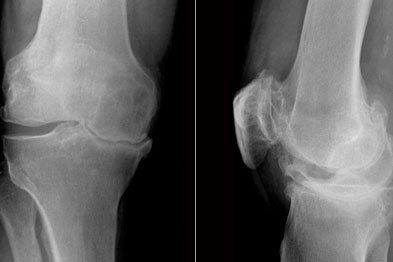

Knee Pain

The knee joint is one of the joints found within the lower limb and is designed for one thing – locomotion.

The knee joint is comprised of the condyles of the femur (thigh bone) and the plateau of the tibia (shin bone) as well as the patella (knee cap) on the femoral condyles. Although the  head of the fibula, located on the outside of the leg, is located near the knee joint, it does not have any weight bearing properties but does provide the articulation for the ankle joint (see here)

Although the knee joint has an important job in locomotion, in particular the forward movement of the free leg during walking, it is a poorly designed joint. The femoral condyles are round which articulates with the flat tibial plateau. Therefore, there are a number of anatomical structures which are designed to provide the knee with more stability…